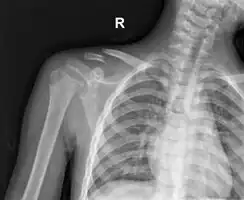

| X-ray of a left clavicle fracture | |

The basic method to check for a clavicle fracture is by an X-ray of the clavicle to determine the fracture type and extent of injury. In former times, X-rays were taken of both clavicle bones for comparison purposes. Due to the curved shape in a tilted plane X-rays are typically oriented with ~15° upwards facing tilt from the front. In more severe cases, a computerized tomography (CT) or magnetic resonance imaging (MRI) scan is taken. However, the standard method of diagnosis through ultrasound imaging performed in the emergency room may be equally accurate in children.[6]